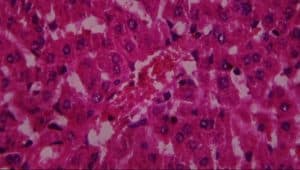

Figure 10: Liver (control) composed of A-hepatocytes, B-sinusoids, C-portal vein and D-bile duct (H&E x 400)

Tissue collection, processing and staining, histopathology: The rats were sacrificed, and the liver was taken at the end of the four weeks study. Blood (5 mL) was collected in sterile bottles for analysis of liver enzymes test and was immediately sent to the University of Benin teaching hospital’s chemical pathology department for biochemical testing. The liver tissue was preserved for 24 hours in 10% buffered formalin before being histologically processed and stained with haematoxylin and eosin using standard procedures.[15] The sections obtained were examined, and photomicrographs were taken using a Leica DM750 research microscope with an attached digital camera (Leica CC50). The tissues were photographed digitally at magnifications of x100.